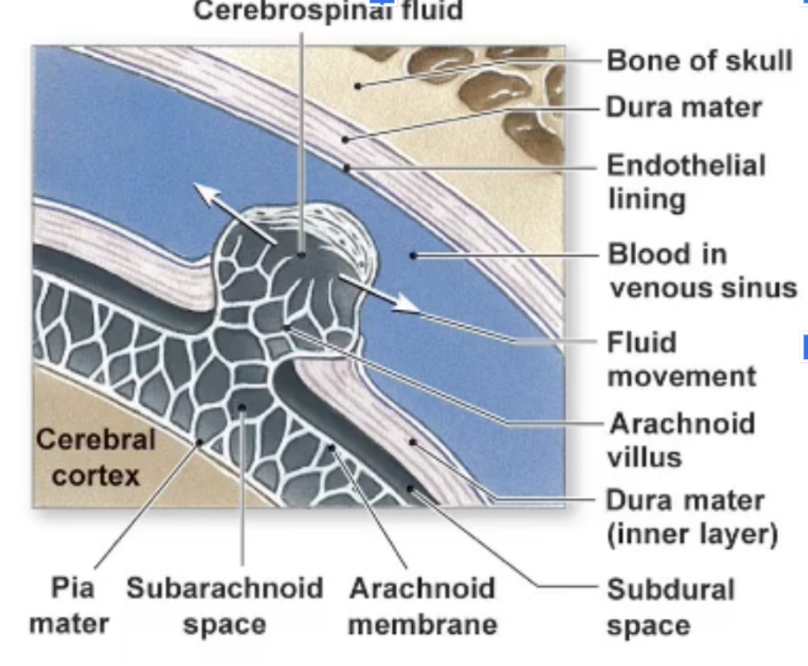

What are the three layers of the Cranial Meninges (thickest to thinnest)?

Dura Mater,Arachnoid Mater, Pia Mater

Which meningeal layer is thin, fibrous, looks like a web, and contains the cerebrospinal fluid (CSF)?

The Arachnoid mater

Where is the CSF located relative to the Arachnoid mater?

In the Subarachnoid space

Which meningeal layer is very thin, the deepest layer, and follows all the grooves of the brain?

The Pia mater.

How is excess CSF drained?

flows into the arachnoid villi where it is drained into dural venousus sinus with the blood